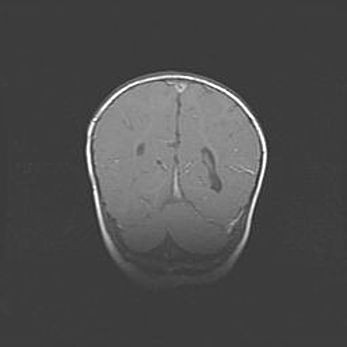

Сообщающаяся гидроцефалия. Кистозная энцефаломаляция головного мозга.

Возраст: 3 месяца 4 дня

Вес: 3100 г

Пол: женский

Окружность головы: 34 см

Срок гестации: 31 неделя

Кистозная энцефаломаляция головного мозга - одна из форм поражения головного мозга в детском возрасте. Характеризуется возникновением множественных и распространённых кист в коре, белом веществе и подкорковых образованиях головного мозга у плодов, новорождённых и детей раннего возраста. Развитие кистозной энцефаломаляции связано с внутриутробной асфиксией и гипотонией, родовой травмой, тромбозом синусов, пороками развития сосудов, инфекциями, сепсисом и другими причинами. Наиболее значимые инфекционные агенты: вирусы простого герпеса, цитомегалии, краснухи, токсоплазмы, энтеробактерии, золотистый стафилококк и другие.